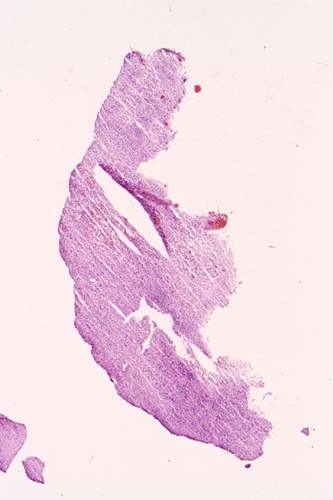

The following photos are taken from representative areas. Panel A and B are taken from intro-operative cytologic preparation. Panel C to F are taken from the frozen section. Panel G to I are taken from formalin fixed paraffin embedded material that has not been frozen. Panel J is fluorescent in situ hybridization (FISH) studies on epidermal growth factor receptor (EGFR).

A. B. C. D. E. F.

G. H. I. J.

Intraoperative consultation: The cytologic preparation provides some very useful information. The cells form poorly defined clumps with elongated, pale pink cytoplasmic processes (Panel A, arrow). The nuclei are elongated, hyperchromatic and resemble "baking potato". Nucleoli are not seen  (Panel B), On the frozen section, a small streak of pale pink tissue suggestive of necrosis is present (Panel C and D). On high-magnification, the viable tumor cells have medium to large amount of cytoplasm and without distinct cytoplasmic border. They are densely packed, with hyperchromatic nuclei and does not form a specific pattern (Panel E). The interphase between the necrotic cells and the viable cells on frozen section is illustrated in (Panel F). The intraoperative diagnosis was "high-grade glial neoplasm with necrosis, probably glioblastoma".

Permenant section: The pathologic changes of the permenant sections are similar to that of frozen. Again, pseudopalisading necrosis is present (Panel G and H). Many of the nuclei are elongated and there is also considerable degree of pleomorphism.  Some of the cells have perinuclear clearing (Panel I). Positive staining for glial fibrillary acidic protein (GFAP) but not synaptophysin is demonstrated by immunohistochemistry. Although the perinuclear halo may suggestive anaplastic oligodendroglioma, the overall pathologic features, particularly the elongated nuclei and degree of pleomorphism, are that of a glioblastoma.